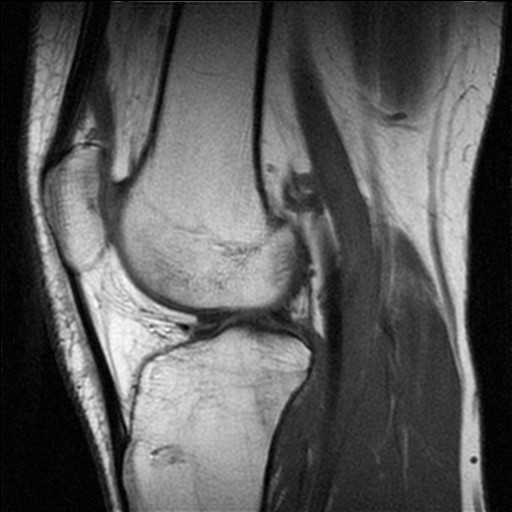

| 의학 영상 | 자기 공명 영상 (MRI) 또는 컴퓨터 단층 촬영 (CT)에서 특정 조직이나 혈관을 강조하여 보여주는 데 사용된다. |

사용된 테이블 또는 함수 및 데이터 소스 선택에 따라 가색상은 원본 이미지의 정보 내용을 증가시킬 수 있다. 예를 들어, 지리 정보를 추가하거나, 적외선 또는 자외선 빛에서 얻은 정보를 결합하거나, MRI 스캔과 같은 다른 소스를 결합할 수 있다.[13]